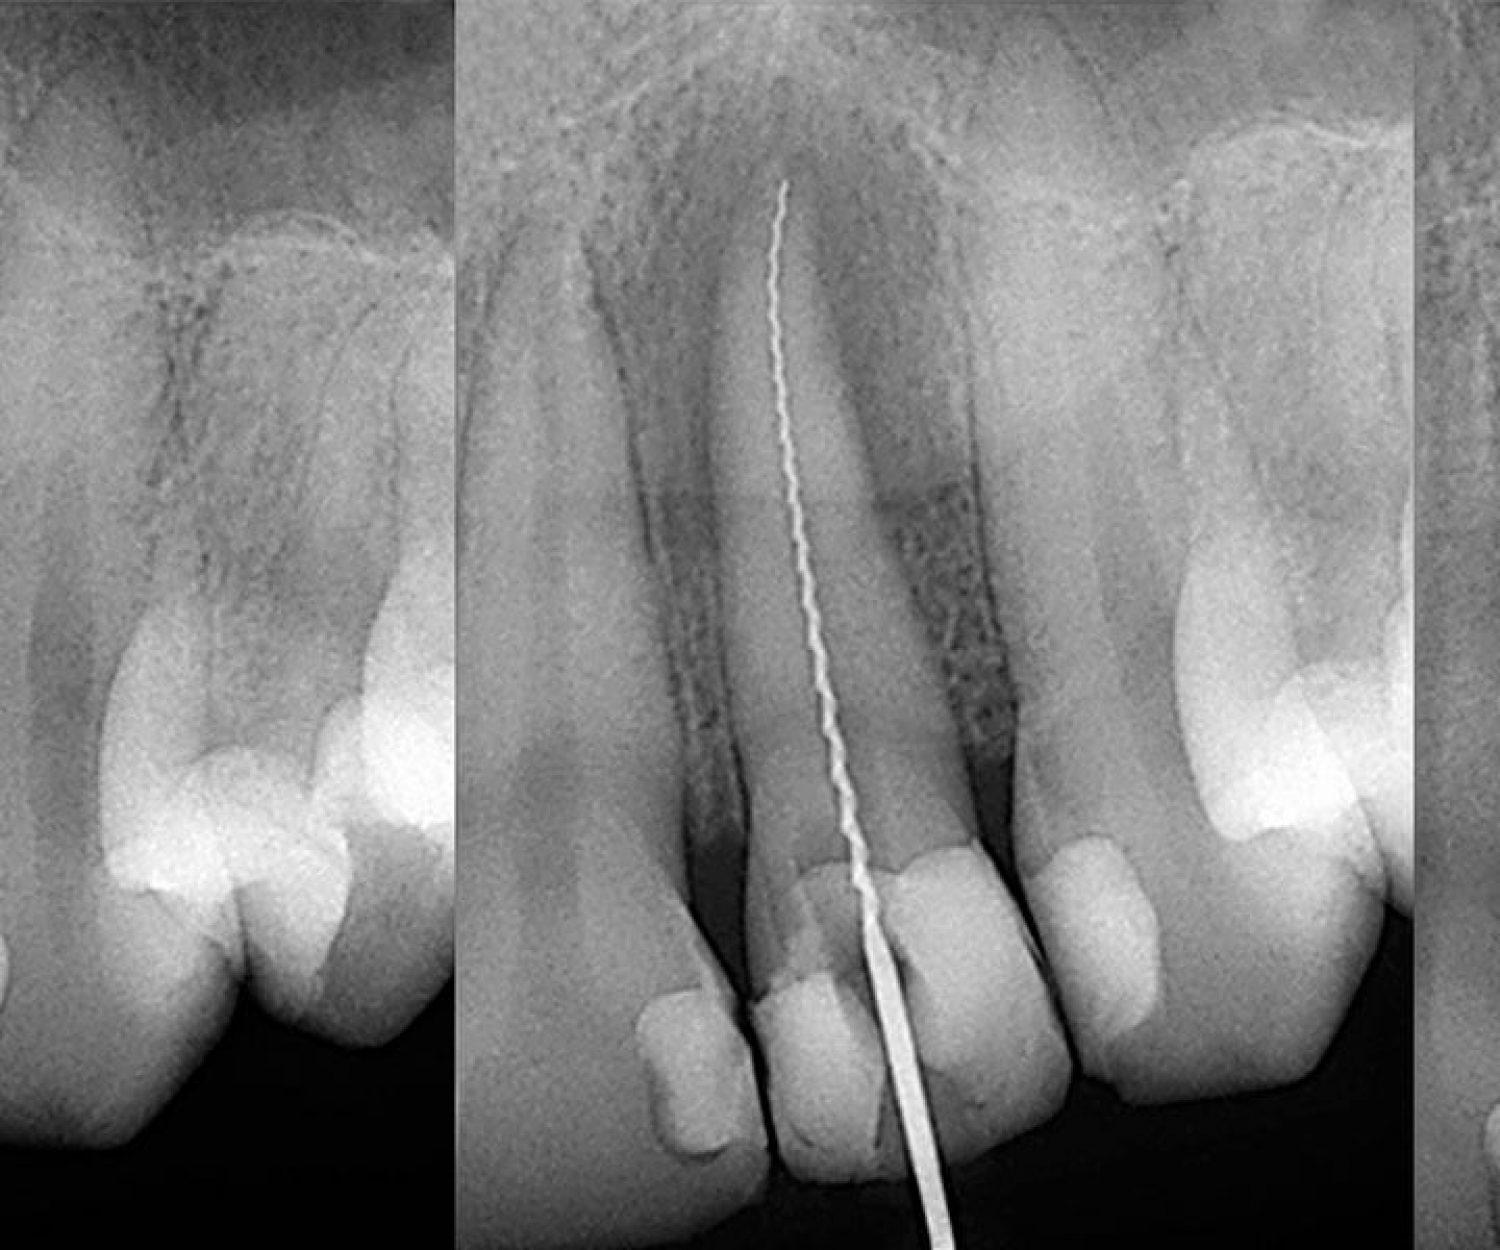

Fractured Teeth

Fractured Teeth can be mended with getting the crowns fixed at Chisel Dental Clinic